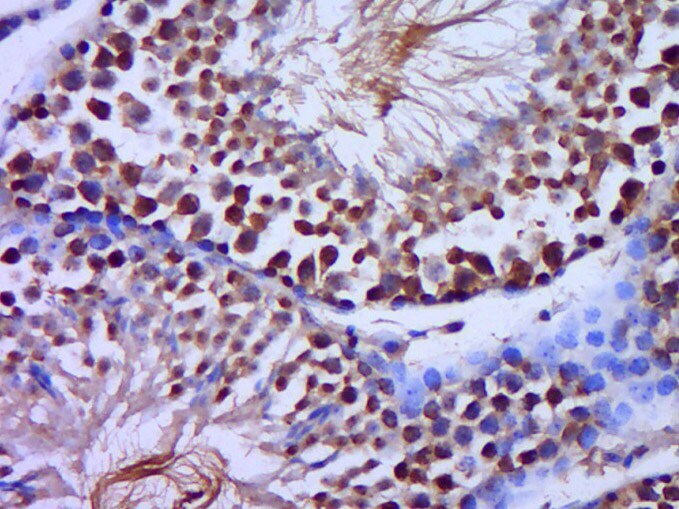

Supportive validation

- Submitted by

- Invitrogen Antibodies (provider)

- Main image

- Experimental details

- Paraformaldehyde-fixed, paraffin embedded Mouse testis; Antigen retrieval by boiling in sodium citrate buffer (pH6.0) for 15min; Block endogenous peroxidase by 3% hydrogen peroxide for 20 minutes; Blocking buffer (normal goat serum) at 37°C for 30min; Antibody incubation with C20orf79 Polyclonal Antibody, Unconjugated (bs-15118R) at 1:400 overnight at 4°C, DAB staining.